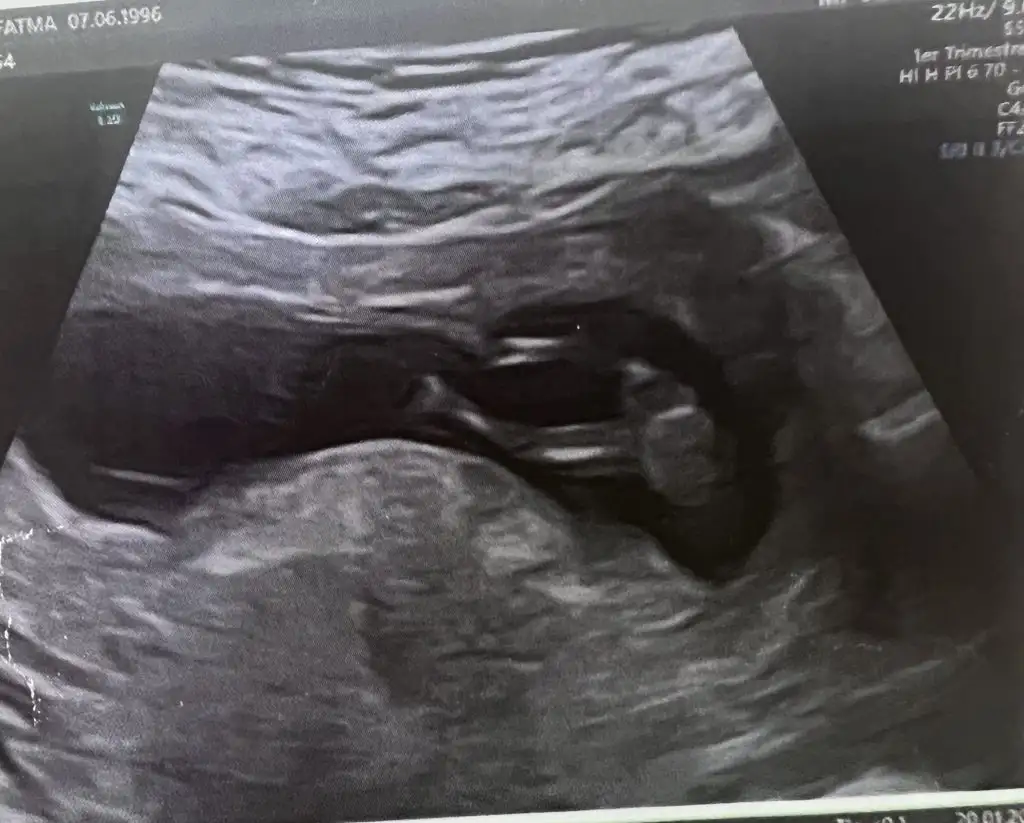

Tam 6 haftalığım bugün kalp atışını duydum ve kesemin fotoğrafını atsam cinsiyet tahmininde bulunabilen olur mu ?

Doktor da kıza benzetti 12 haftalık, çıkıntı vs olmadığı için mi acaba 🥰 neye göre yorumladınız teşekkürler 🙏

Benim doktorumda 12 haftalıkken kız demişti öyle de sonuclandı☺️ Bacak arasında herhangi bir şey yok bizimkide öyleydi ama normal durusta kız bebeklerde de çıkıntı olabiliyor sadece o cıkıntının düz gitmesi lazım yukarı dogruysa erkek oluyo bizimkinin düzdü o çıkıntı 🥰 ama yüksek ihtimal sizinde kız yakında bacak arasında 3 çizgi görüceksin eger kesin kızsa ☺️

tahmin yapabilir misiniz kızlar 16+3 göstermedi 🥲